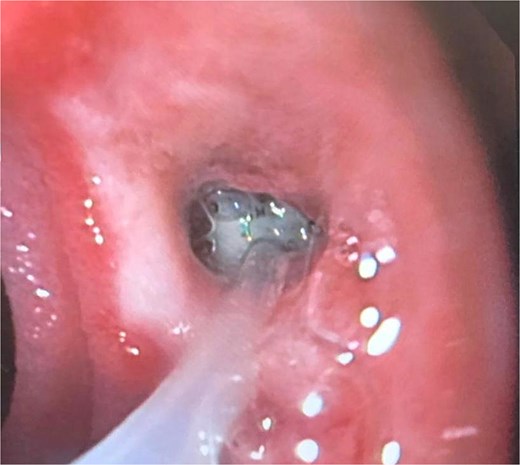

At the last endoscopy 30 days later, 100% granulation tissue was observed with no evidence of a fistulous orifice (Fig. 3). A leak test by fluoroscopy showed no leakage, allowing the initiation of a liquid diet for 15 days, progressing to a normal diet after one month. Follow-up endoscopy showed no pathological findings.

After follow-ups and sponge replacements, the closure of the fistulous defect can be observed.